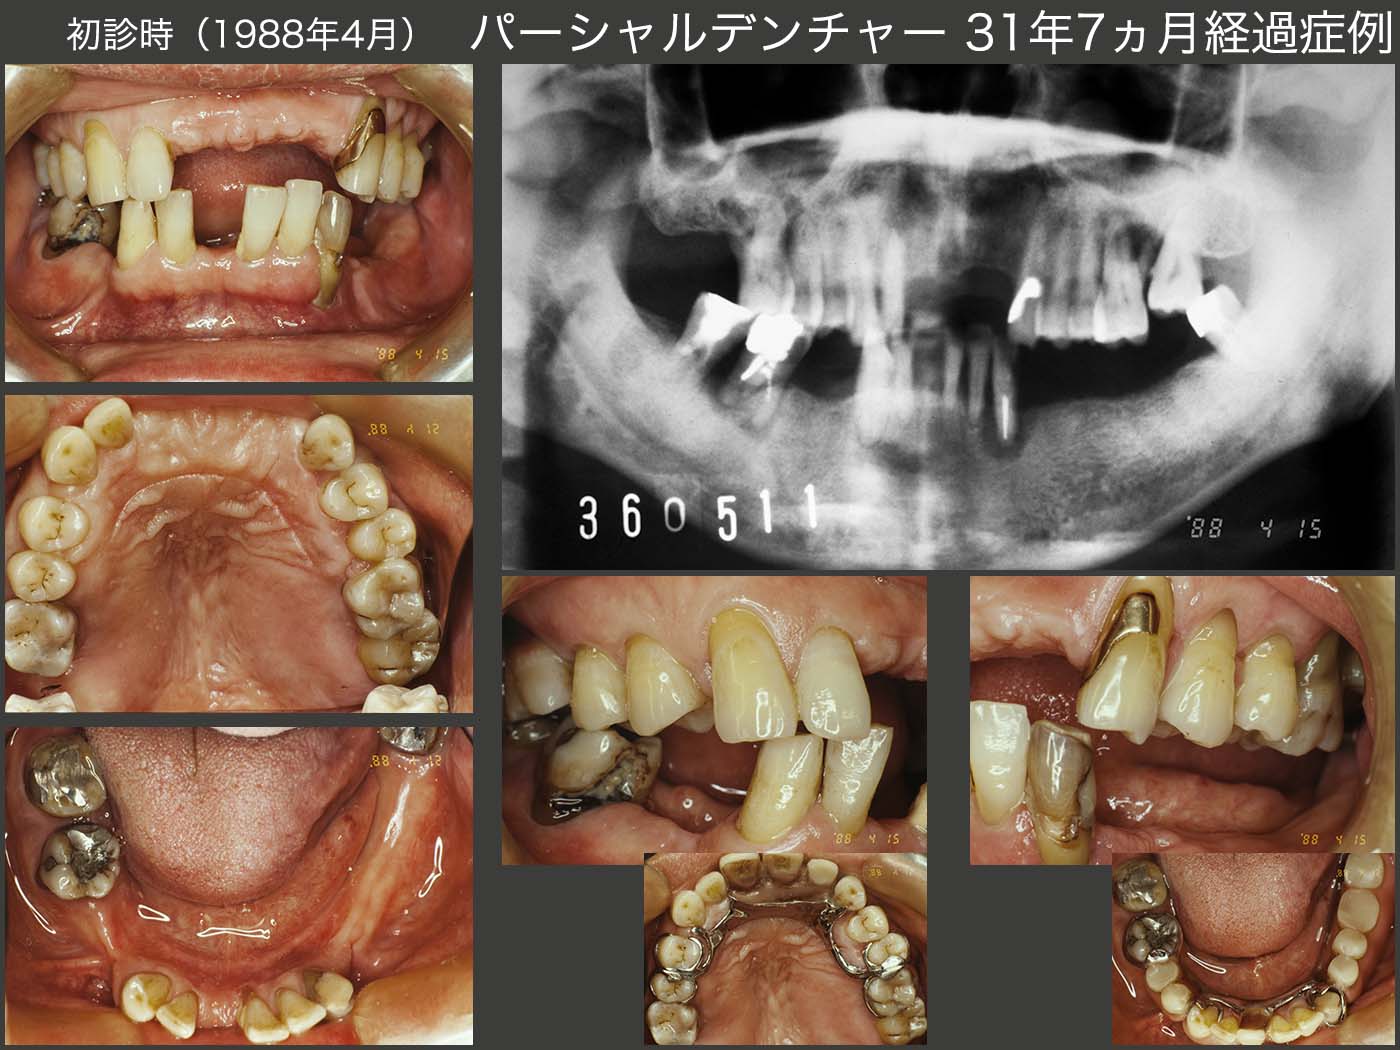

21.パーシャルデンチャー31年7ヵ月経過症例

1988年4月初診,51歳男性.主訴は,左下3の歯肉が腫れた.右上6,左上6,7,左下3および右下6,7の歯周ポケットは10mm以上あり,当時の私の実力では保存不可能であった.特に,右側の上下6を抜去したため,臼歯部の咬合支持がなくなり,下顎位は右側の上下2,3で保持されていた.と言っても,当時の私は咬合支持と言う概念はなく,この後下顎位を全く無視した治療を行ってしまった.

保存不可能な歯の抜去後,上下に暫間義歯を装着した.この時は右側の上下2,3が咬合しており下顎位は正しいと思われる.